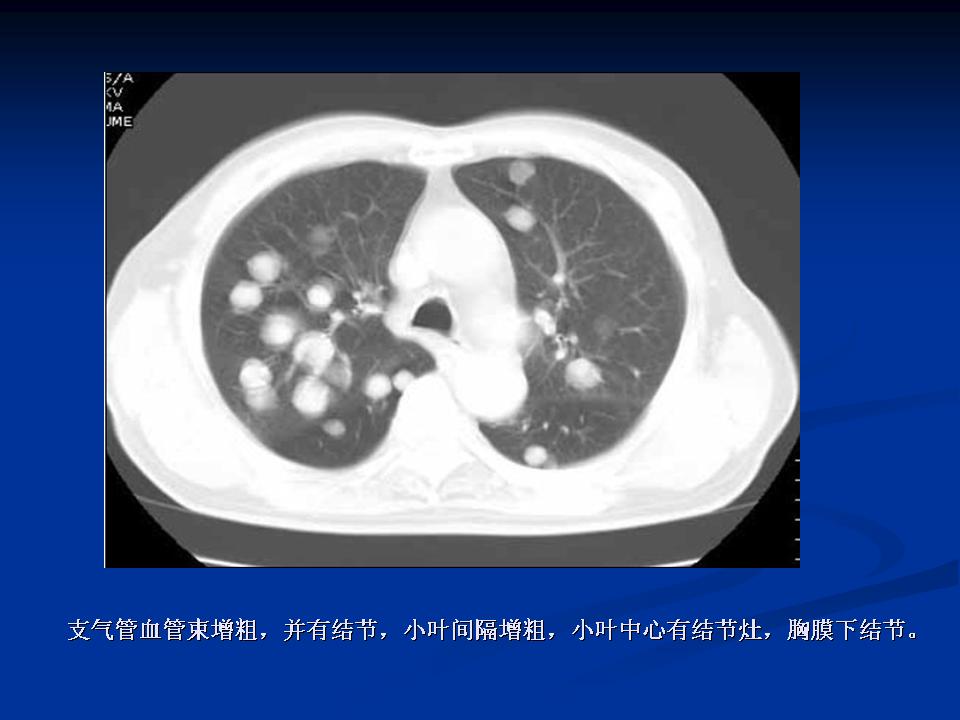

肺转移瘤与韦格肉芽肿影像鉴别